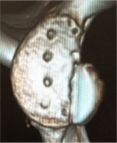

脱臼を繰り返すとどうなるか

脱臼を繰り返すと、前方を支える軟部組織(関節唇、関節包)がさらに損傷していき、最終的には受け皿の骨(肩甲骨)が欠けて小さくなったり、上腕骨の後方に大きな骨欠損が生じたりします。その結果、スポーツ活動はもちろん、日常生活にも大きな影響が出て生活の質(QOL)が著しく低下してしまいます。

X線 ( レントゲン )や MRI (磁気共鳴画像)を用いて、骨の位置や周囲の軟部組織の損傷を確認します。必要に応じて CT 検査も行います。